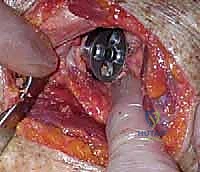

Additional Intraoperative Imaging & Surgical Steps